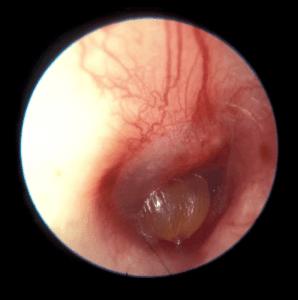

Diagnostika. Otoskopuojant matyti paburkusi, paraudusi išorinė klausomoji landa. Jei procesas ypač aktyvus, galime net nematyti landos spindžio, būgnelis dažnai būna paraudęs, sustorėjęs. Landoje stebimos klampios, dvokiančios išskyros.

Pav. Gydymas. Gydant išorinį otitą būtina kruopščiai išvalyti išorinę klausomąją landą. Jei landos spindis siauras dėl ryškios edemos, rekomenduojama iš pradžių taikyti marlinius tamponėlius, suvilgytus susp. hydrocortisoni, antibiotikų ar priešgrybeliniu tepalu priklausomai nuo sukėlėjo rūšies. Dažniausiai naudojami tepalai turintys savo sudėtyje aminoglikozidų (neomicino – Ung. Baneocin) arba antibiotiko ir kortikosteroido mišiniai (ung. Flucinar, ung. Fucicort). Tamponėlį reikėtų keisti kas 24–48 valandas. Vėliau, atslūgus landos paburkimui, į ausį galima lašinti antibiotikų tirpalus (fluorochinolonų grupės- Ciloxan 0.3%, sudėtinių antibiotikų ir kortikosteroidų lašus- Maxitrol, Dexona), taikyti lazerioterapiją. Jei uždegimas palietė vidurinę ausį ir vietinis antibiotikų poveikis per silpnas, vangi ligos eiga, uždegimas užtruko, pasikartojo po prieš taikyto vietinio gydymo rekomenduojama skirti sisteminius antibiotikus. Taip pat svarbu paskirti stiprius skausmą malšinančius preparatus, nes skausmas esant išoriniam ausies uždegimui – pagrindinis ir nemaloniausias nusiskundimas.